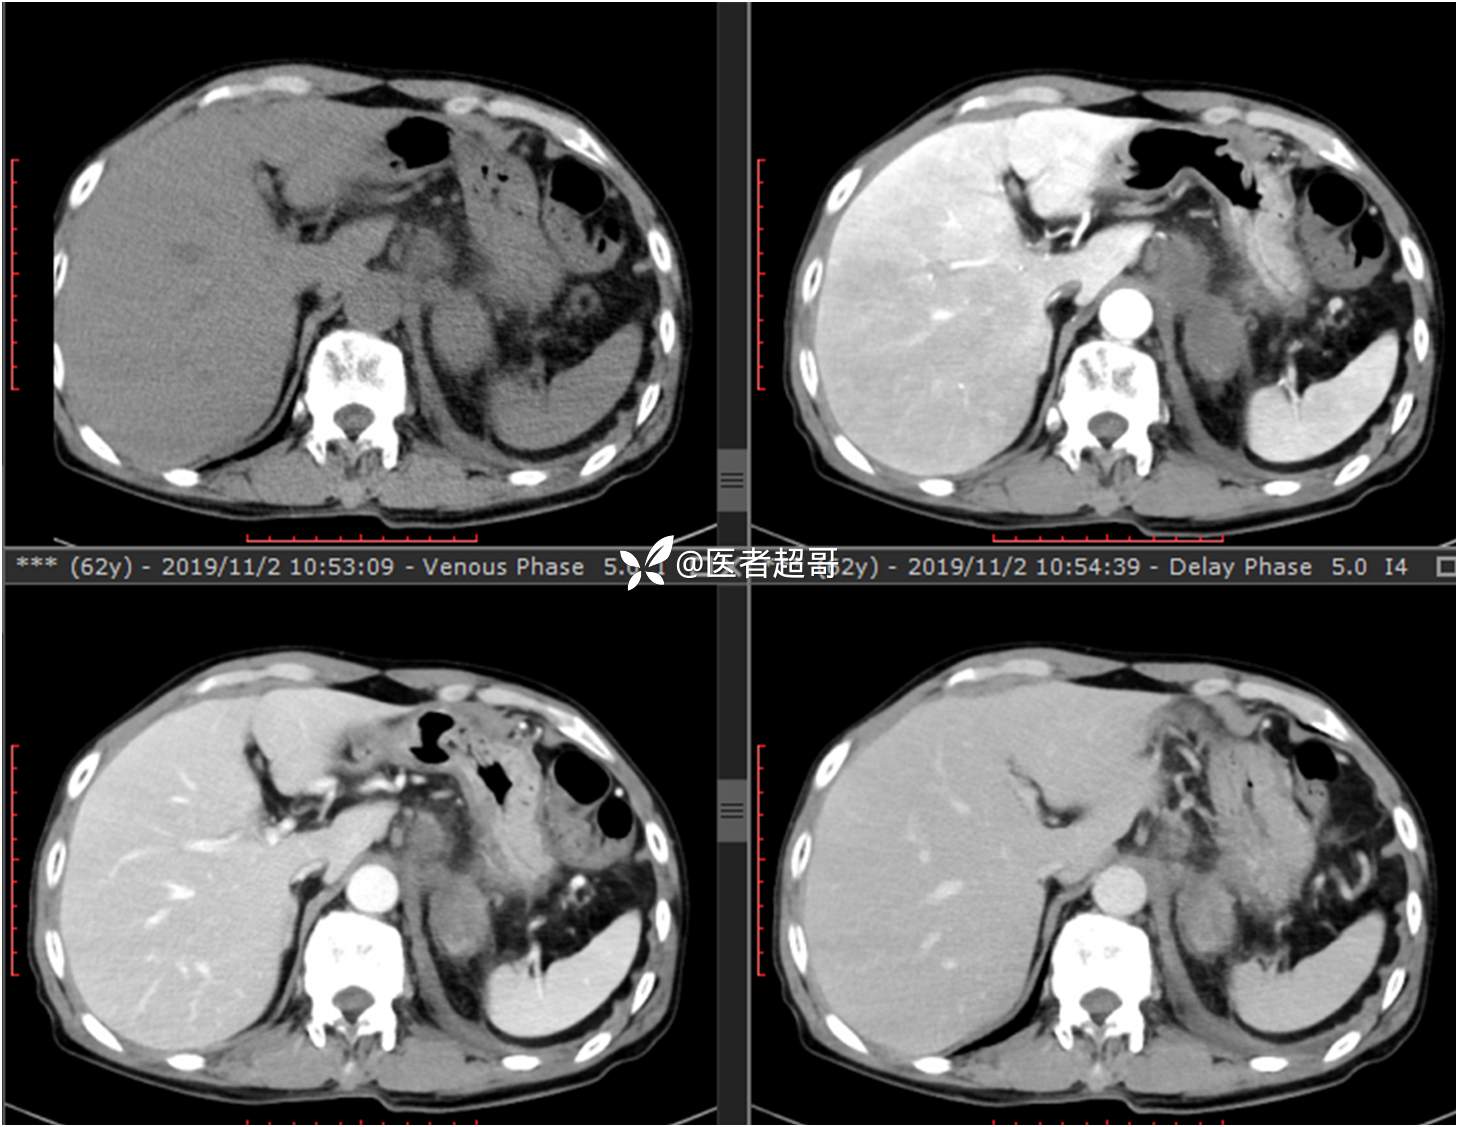

现病史:患者于1月前无明显原因及诱因出现左上腹部疼痛,为间断性疼痛,无恶心、呕吐,无寒战、高热,无腹胀、腹泻等伴随症状,在外未行特殊处理,患者于1周前自觉疼痛加重,为求诊治患者曾就诊于市东城医院,行全腹部强化CT提示:左肾上腺区肿块,符合恶性肿瘤侵犯左肾、胰腺及腹膜后大血管CT表现,行保守治疗,症状缓解,今患者为求进一步诊治,来我院就诊,行腹膜后占位穿刺活检病理提示:(腹膜后占位穿刺)小细胞背景内见细胞浆红染的神经节样细胞,建议到病理科加做免疫组化进一步明确诊断,遂以“腹膜后肿物”收入院,患者自发病以来,神志清,精神可,饮食、睡眠差,大小便正常,体重未见明显改变。